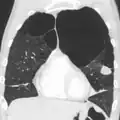

A chest X-ray is not useful to establish a diagnosis of COPD, but it is of use in either excluding other conditions or including comorbidities such as pulmonary fibrosis and bronchiectasis. Characteristic signs of COPD on X-ray include hyperinflation (shown by a flattened diaphragm and an increased retrosternal air space) and lung hyperlucency.[5] A saber-sheath trachea may also be shown that is indicative of COPD.[111]

A CT scan is not routinely used except for the exclusion of bronchiectasis.[5] Pulse oximetry measurement of peripheral oxygen saturation is recommended in people with clinical signs of respiratory failure or right heart failure.[5] An analysis of arterial blood is recommended in those with a peripheral oxygen saturation of 92% or less to determine actual blood oxygen level and assess for high levels of carbon dioxide in the blood, which may have therapeutic implications such as need for non-invasive ventilation or oxygen supplementation.[10] WHO recommends that all those diagnosed with COPD be screened for alpha-1 antitrypsin deficiency.[40]